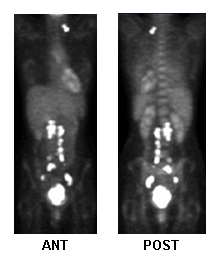

Fluorodeoxyglucose-PET for treatment planning, metastatic activity

From the collection of Neil S. Horowitz, MD; used with permission

See this image in context in the following section/s:

Cervical cancer